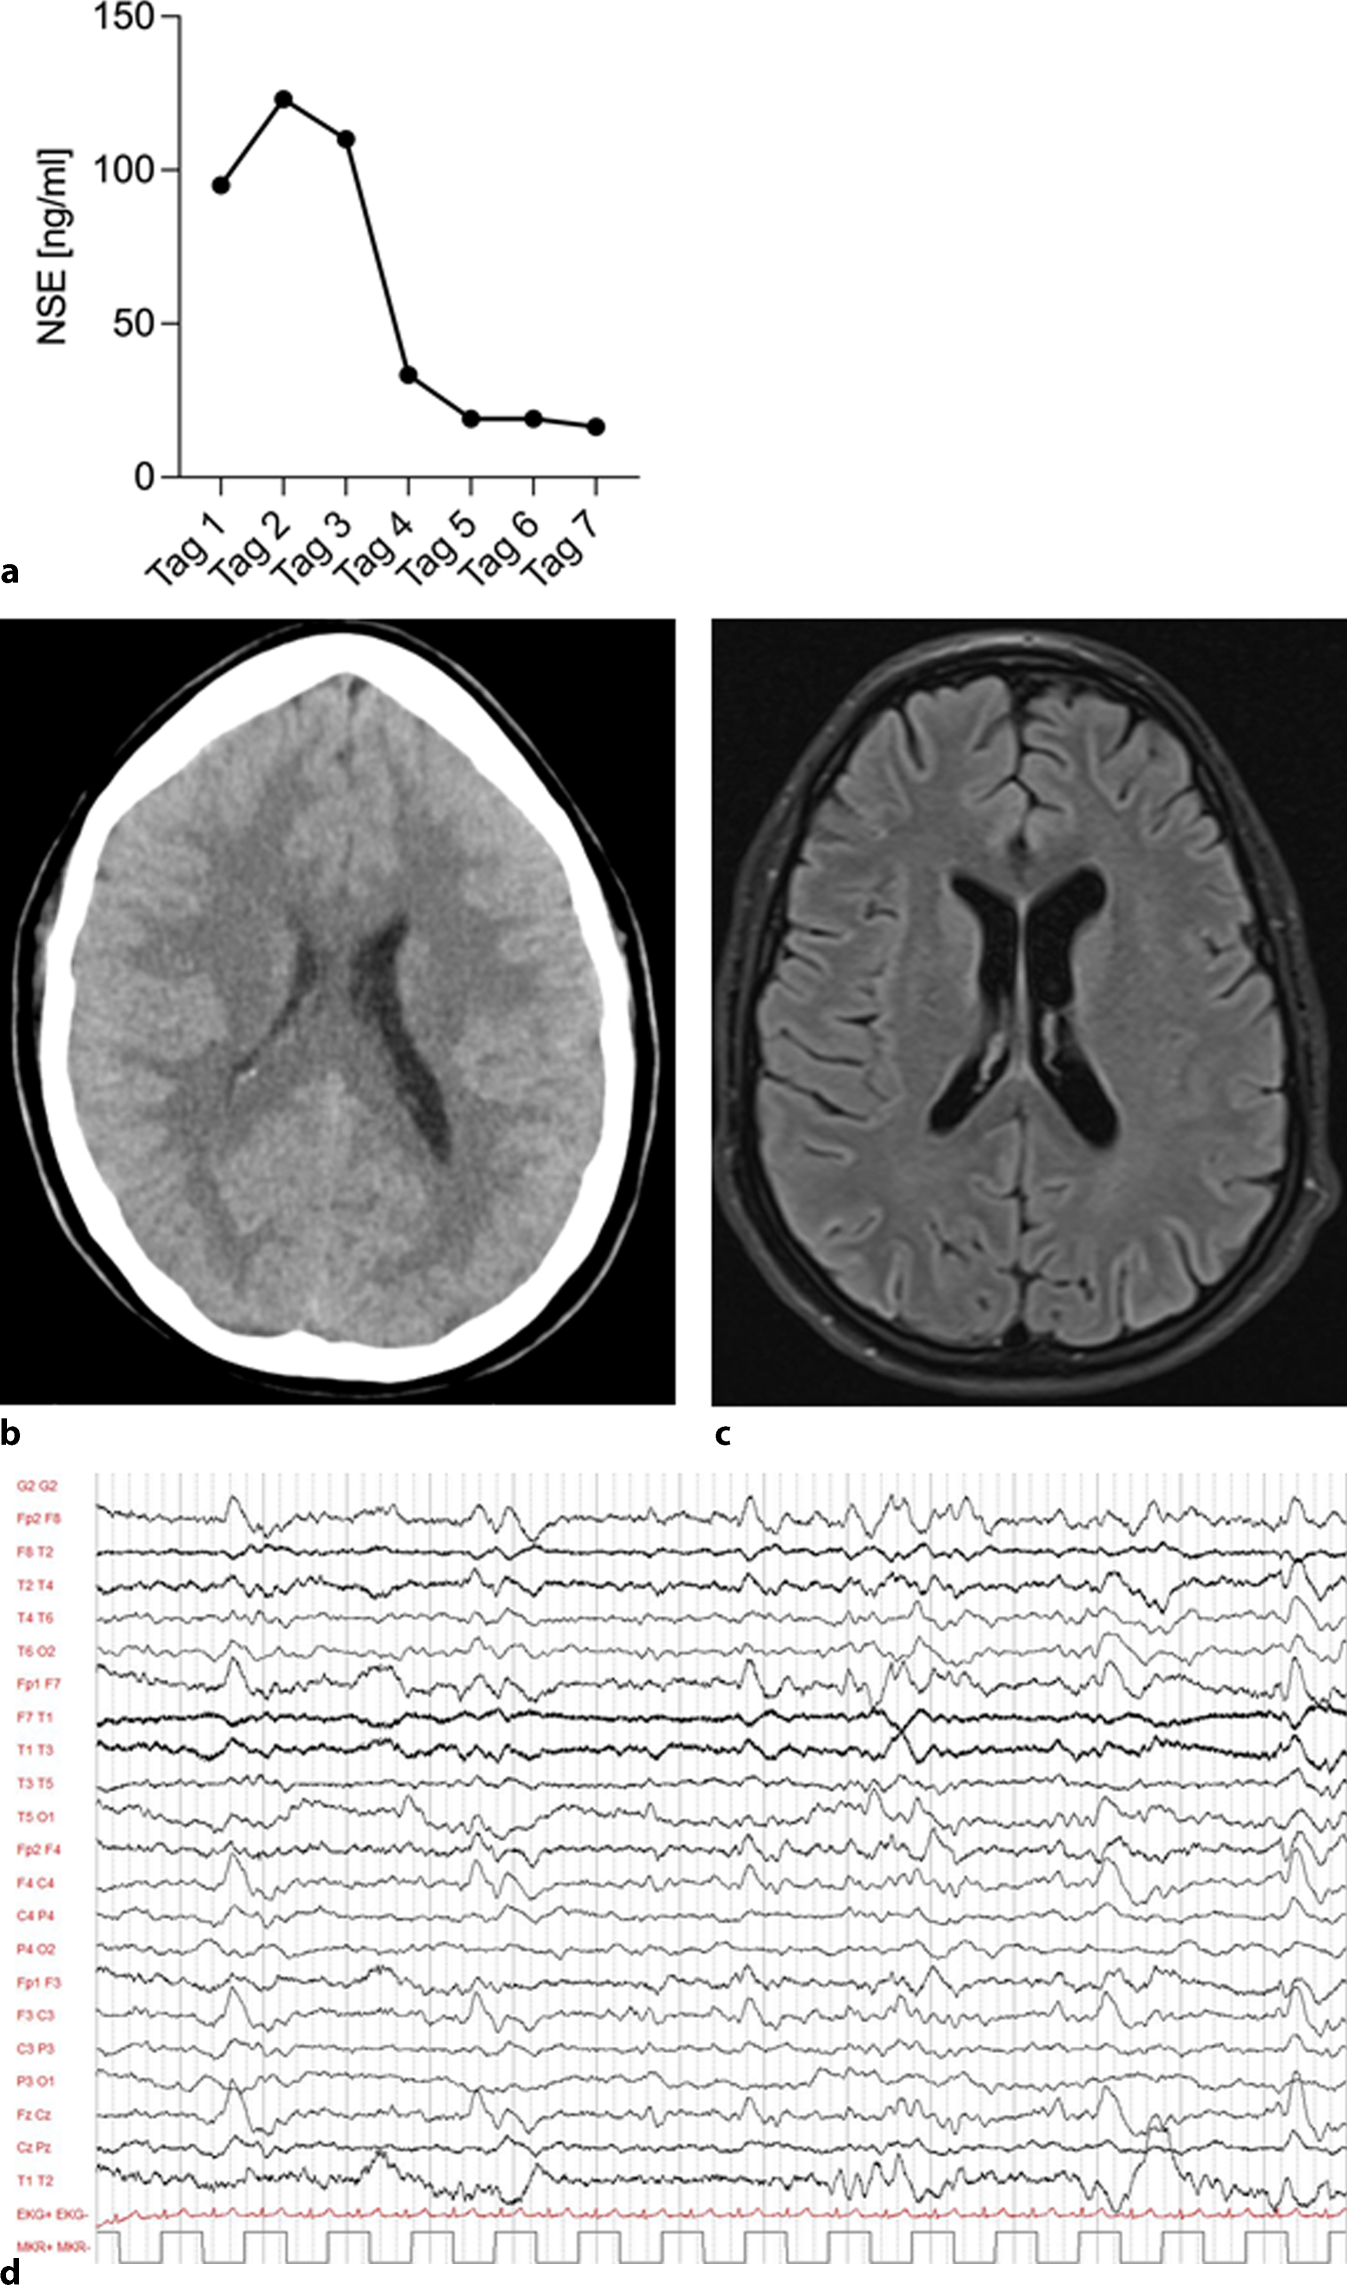

Ein NSE-Wert von 123 ng/ml (Abb. 2a) wurde 48 h nach Reanimation ermittelt, gefolgt von einem weiteren kranialen CT am selben Tag (Abb. 2b). Dieses zeigte eine altersgerechte Hirndarstellung ohne Hinweise auf einen hypoxischen Schaden oder einen erhöhten Hirndruck. Der NSE-Serumspiegel zeigte sich im Verlauf fallend (Abb. 2a). Bei einem akuten Nierenversagen aufgrund eines Crush-Syndroms (Myoglobin max. 206,3429 nmol/l, Grenzwert 3,3143 nmol/l; Kreatininkinase [CK] max. 220,8 µmol/sl, Grenzwert 2,833 µmol/sl) wurde extern eine Nierenersatztherapie mit Hämoadsorption begonnen. Nach 21 Tagen konnte die Dialyse beendet werden. Die Kreatininwerte zeigten sich im Anschluss regredient (Abb. 1e). Der Weaningprozess von der Beatmung gestaltete sich anspruchsvoll, konnte jedoch nach 10 Tagen erfolgreich abgeschlossen werden. Die weiterführende Diagnostik zur Abschätzung der neurologischen Prognose mittels kranialer magnetresonanztomographischer(MRT)-Untersuchung (Abb. 2c), Elektroenzephalogramm (EEG; Abb. 2d) sowie Medianus-SEP (Tab. 1) verblieb ohne relevante Auffälligkeiten.

Abb. 2

a NSE-Verlauf beginnend am 1. Tag nach CPR; b kraniales CT an Tag 3 nach CPR; c kraniales MRT am 20. Tag nach CPR; d EEG am 13. Tag nach CPR